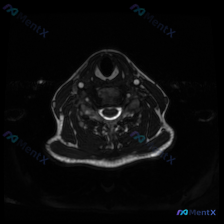

分享一张颈椎MRI T2轴位片,整理了完整的读片和分析思路,大家一起讨论看看。 病例基本影像信息 这是一张颈椎椎间盘水平的T2加权轴位图像,图像对比度良好,脑脊液呈高信号,脊髓中等信号,椎间盘中低信号,没有明显严重伪影,解剖层次清晰。 系统观察各个结构: 1. 骨骼关节:椎体形态完整,椎体后缘可见轻...

刚整理了一份很有启发的颈椎MRI读片病例,核心问题是“这张图里能观察到椎间盘病变吗?”,把完整分析思路分享给大家。 影像基本信息 这是一张颈椎MRI轴位T2加权图像,我们先把观察到的结构特征理清楚: 1. 椎体与椎管:脑脊液呈高信号,脊髓居中,形态规整,内部没有明显异常信号(无水肿灶);椎体后缘有轻...

整理了这张颈椎MRI读片病例和完整分析思路,分享给大家一起讨论 病例与影像基础信息 本次读片对象为颈椎MRI-T2序列轴位单张影像,核心问题是观察图像是否存在椎间盘病变: 1. 影像质量良好,对比度清晰,脊髓、脑脊液、软组织结构显示清楚,无明显运动伪影,扫描层面为颈椎中下段水平 2. 核心影像表现:...

刚看到一个有意思的读片病例,用户提供了一张颈椎MRI-T2序列轴位图像,明确提问是围绕「椎间盘病变」的观察,整理一下完整分析思路分享给大家。 一、影像基本信息 这是颈椎中下段的MRI-T2加权轴位图像,我们先按层次梳理客观观察结果: 1. 椎管与脊髓:脊髓位于椎管中央,形态规则,内部信号没有异常高/...